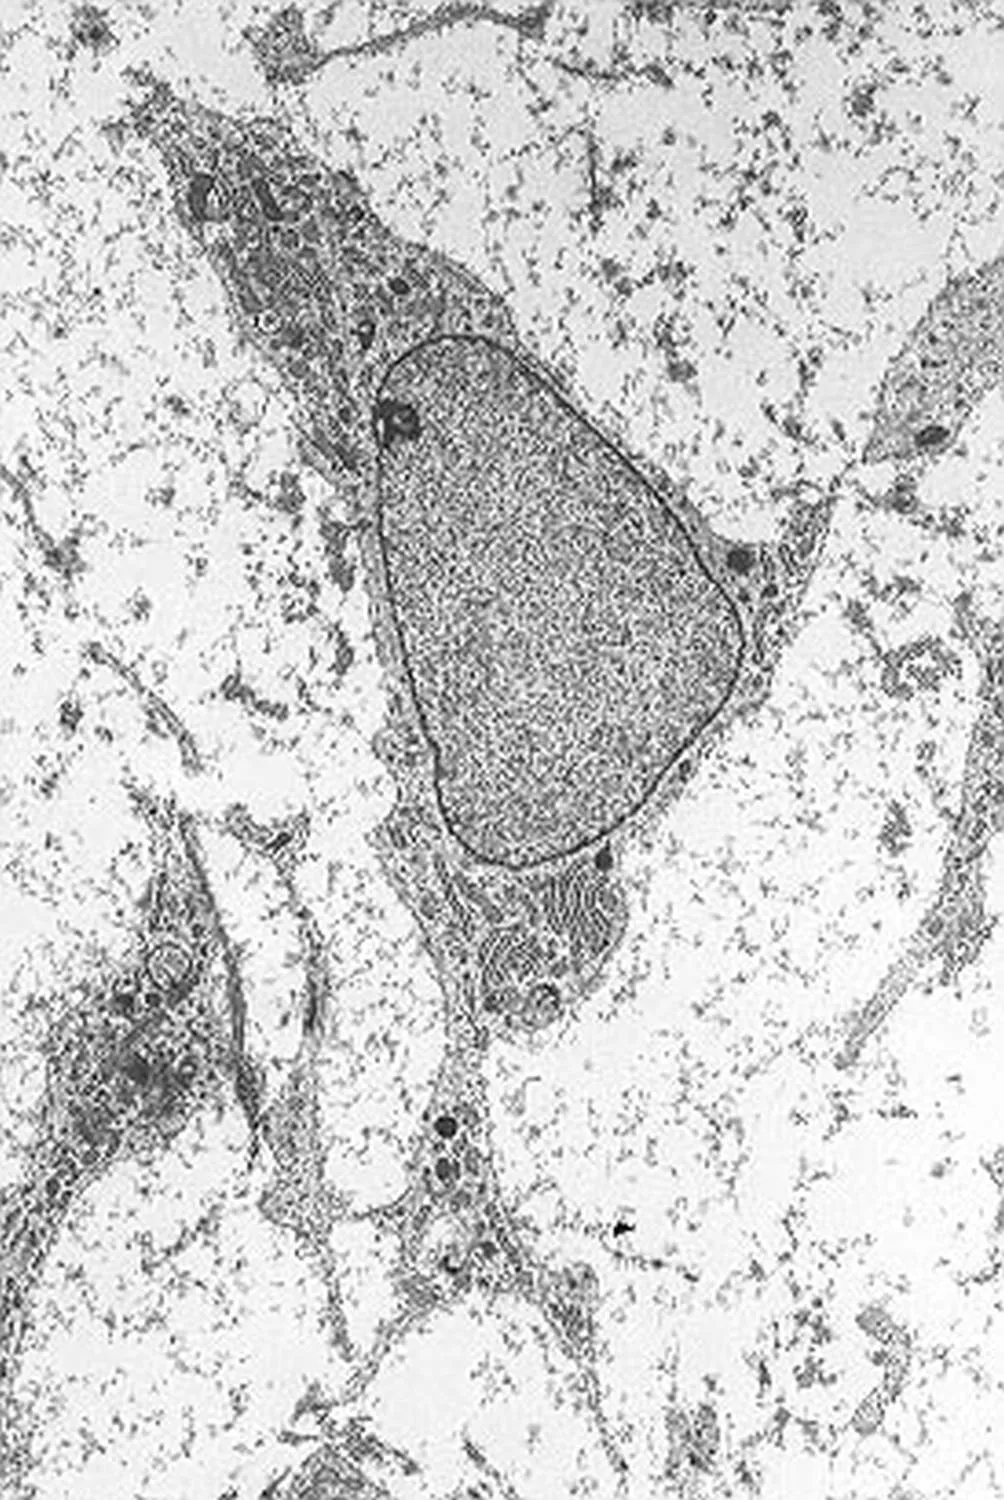

Az őssejteknek számos típusa ismert, a felnőtt szervezetből nyert mezenchimális őssejtek laboratóriumi körülmények között fenntarthatók és szaporíthatók.

A HCEMM kutatóintézet kutatói - Pankotai Tibor és Veréb Zoltán - mezenchimális őssejteket vizsgáltak, amelyek több különféle kötőszövet létrehozásáért felelnek, és amelyeket gyakran alkalmaznak a ma használatos eljárásokban.

A kutatók munkája rámutat arra, hogy a vizsgált őssejtek örökítőanyaga a terápiás felhasználásuk folyamán gyakran károsodik: ebben szerepe van az életkornak, a gyulladt, beteg környezetnek, ahová a sejteket helyezik, és az "átprogramozásnak", ami szükséges ahhoz, hogy az őssejt a kívánt sejttípusokat hozza létre.

A kár jelenlétét a kutatók számára a sejtek DNS-javító rendszerének működésbe lépése árulta el, a sejtek tehát igyekeznek megjavítani magukat, de ez a folyamat nem tökéletes, és a halmozódó hibák egy idő után akadályozzák az őssejteket abban, hogy a feladatukat megfelelően ellássák.